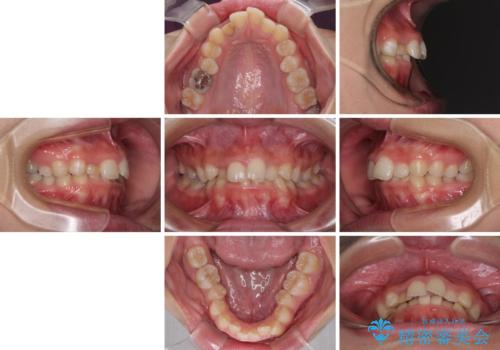

- 前歯の歯並びと不自然な色をした前歯のクラウンを気にして来院された患者様です。

上下前歯の歯列不正はインビザラインにより歯列を整え、その後に、前歯をオーダーメイドタイプのオールセラミッククラウンにて補綴治療することとしました。

前歯のデコボコを一番気にしていらっしゃいましたが、矯正治療により下顎前歯が隠れるほどのディープバイトも一緒に改善され、奥歯に負担のかかりにくい咬み合わせとなりました。